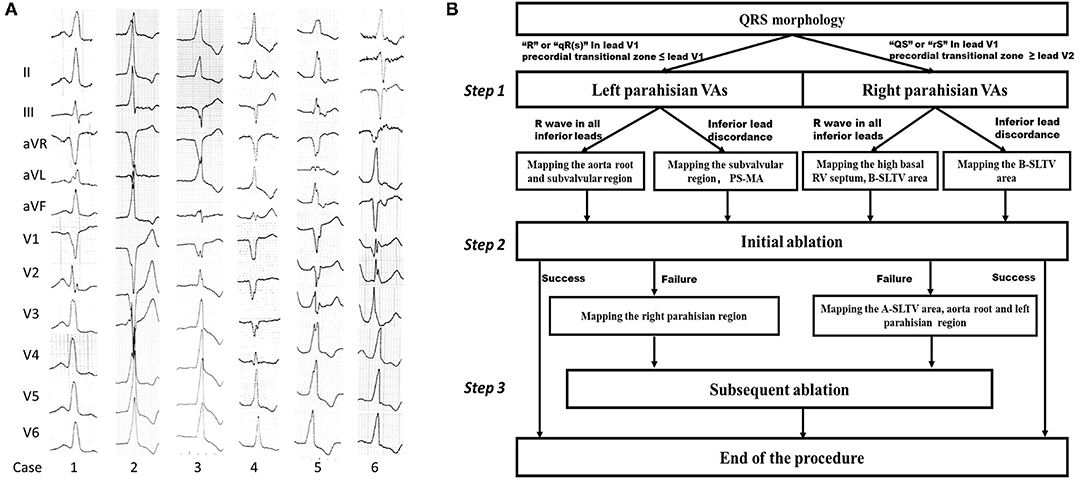

The baseline demographic parameters in all patients and in those with right / left PHVAs were listed in Table 1, respectively. There were 18 patients with hypertension, 5 with type 2 diabetes mellitus, 2 with mild coronary artery atherosclerosis detected by computed tomographic angiography, and 3 with left ventricular ejection fraction 40–50%. Forty-two patients presented with isolated PVCs and 1 with concomitant non-sustained VT. An average of 1.3 ± 0.5 AADs were used per patient. The clinical VA was primarily diagnosed as left PHVA in 3 patients and as right PHVA in the remaining 40 patients based on the ECG. PHVA was successfully ablated from the left side in 4 of 40 patients with ECG-diagnosed right PHVA, and was re-grouped as left PHVA. Totally there were 36 with right PHVA and 7 with left-sided VA.

Right PHVA Ablation

RF ablation by the B-SLTV approach succeeded in 24 (66.7%) of 36 patients with right PHVA, and failed in the remaining 12 patients (Figure 5). The electrocardiographic and procedural data were compared between successful and unsuccessful B-SLTV ablation in Table 2. There was significant greater target -HB distance and lower prevalence of junctional beats in patients with successful B-SLTV ablation than in those without. ECG morphologies, the local ventricular activation preceding QRS onset (V-QRS), proportion of small HB potential at the target, average RF power, RF duration, number of RF delivery and fluoroscopy time were comparable between successful and unsuccessful B-SLTV ablation.

Figure 5. The schematic diagram showing the acute procedural results of right and left PHVA ablation. The yellow dots represented successful cases by the B-SLTV approach and those by trans-aortic retrograde ablation. The purple dots represented success cases by the adjunctive A-SLTV approach. White dots represented cases with ablation failure.

Among the electrocardiographic and procedural parameters, target-HB distance was the only factor that could predict successful B-SLTV ablation for right PHVA (OR 1.703; 95% CI 1.084–2.676, P = 0.02). ROC analysis showed target-HB distance cutoff value was 4.5 mm (sensitivity 66.7% and specificity 83.3%; Area under the curve = 0.773, 95% CI 0.614–0.931, P = 0.01). There was no significant difference in RF power and duration between cases with target-HB distance > 4.5 mm and those with target-HB distance ≤ 4.5 mm (35.0 ± 2.3 vs. 36.0 ± 3.4 W, P = 0.34; 155.5 ± 38.1 vs. 146.3 ± 34.2 s, P = 0.76, respectively).

Subsequent ablation in 12 patients with unsuccessful B-SLTV ablation was listed in detail in Supplementary Table 1. A-SLTV ablation successfully abolished the clinical VA in 6 of them. Totally procedural success was achieved in 30 (83.3%) of 36 patients with right PHVA. The remaining 6 patients experienced ablation failure even after thorough mapping and ablation at the neighboring structures (RVOT and three coronary cusps at the aortic root) and the left- parahisian region.

Left PHVA Ablation

Sub-aortic valve ablation was successful in all seven patients with left PHVA. In each of 4 patients with failed right parahisian ablation, the V-QRS time at the left-sided target was greater than that at the right-sided target (27 vs. 24, 31 vs. 29, 16 vs. 14, 33 vs. 31 ms, respectively). Compared with right PHVA, left PHVA exhibited higher proportion of precordial transition ≤lead V2 and lower proportion of QS shape in lead V1 on ECG recordings (Table 2). The procedural parameters were comparable except that the target-HB distance was greater in left sided group than that in right-sided group.